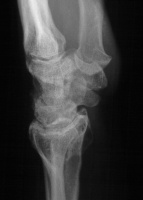

Preoperative Xrays:

Image Image Image